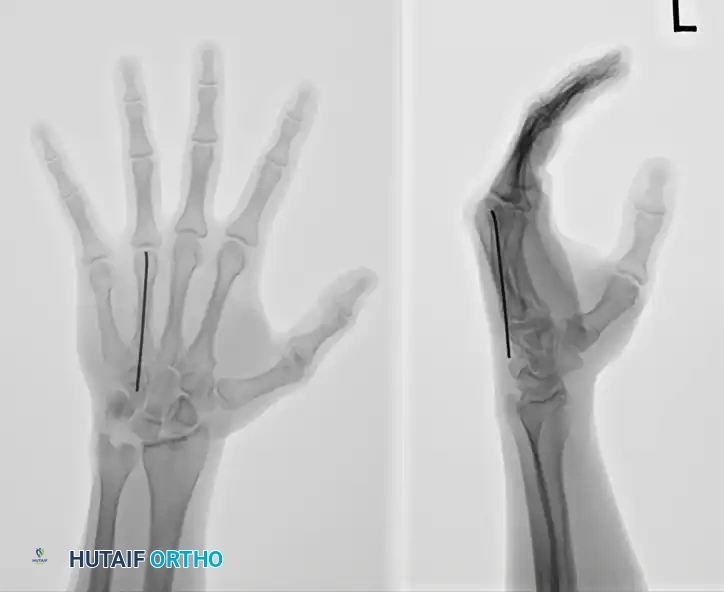

FIGURE 67-35A: Preoperative AP radiograph of a fifth metacarpal neck fracture.

FIGURE 67-35B: Preoperative oblique radiograph demonstrating displacement.

FIGURE 67-35C: Preoperative lateral radiograph showing 80-degree apex dorsal angulation and rotational deformity.

FIGURE 67-35D: Postoperative AP radiograph after reduction to acceptable angulation using a single intramedullary pin.

FIGURE 67-35E: Postoperative oblique radiograph confirming alignment.

FIGURE 67-35F: Postoperative lateral radiograph demonstrating restoration of the volar cortex.